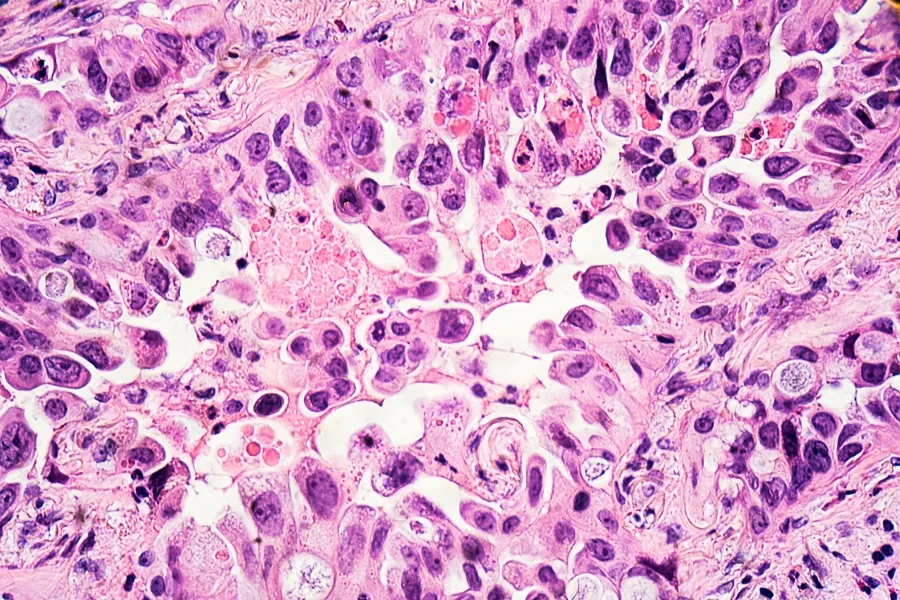

Lung cancer - adenocarcinoma

Image credit: rightdx via Getty Images